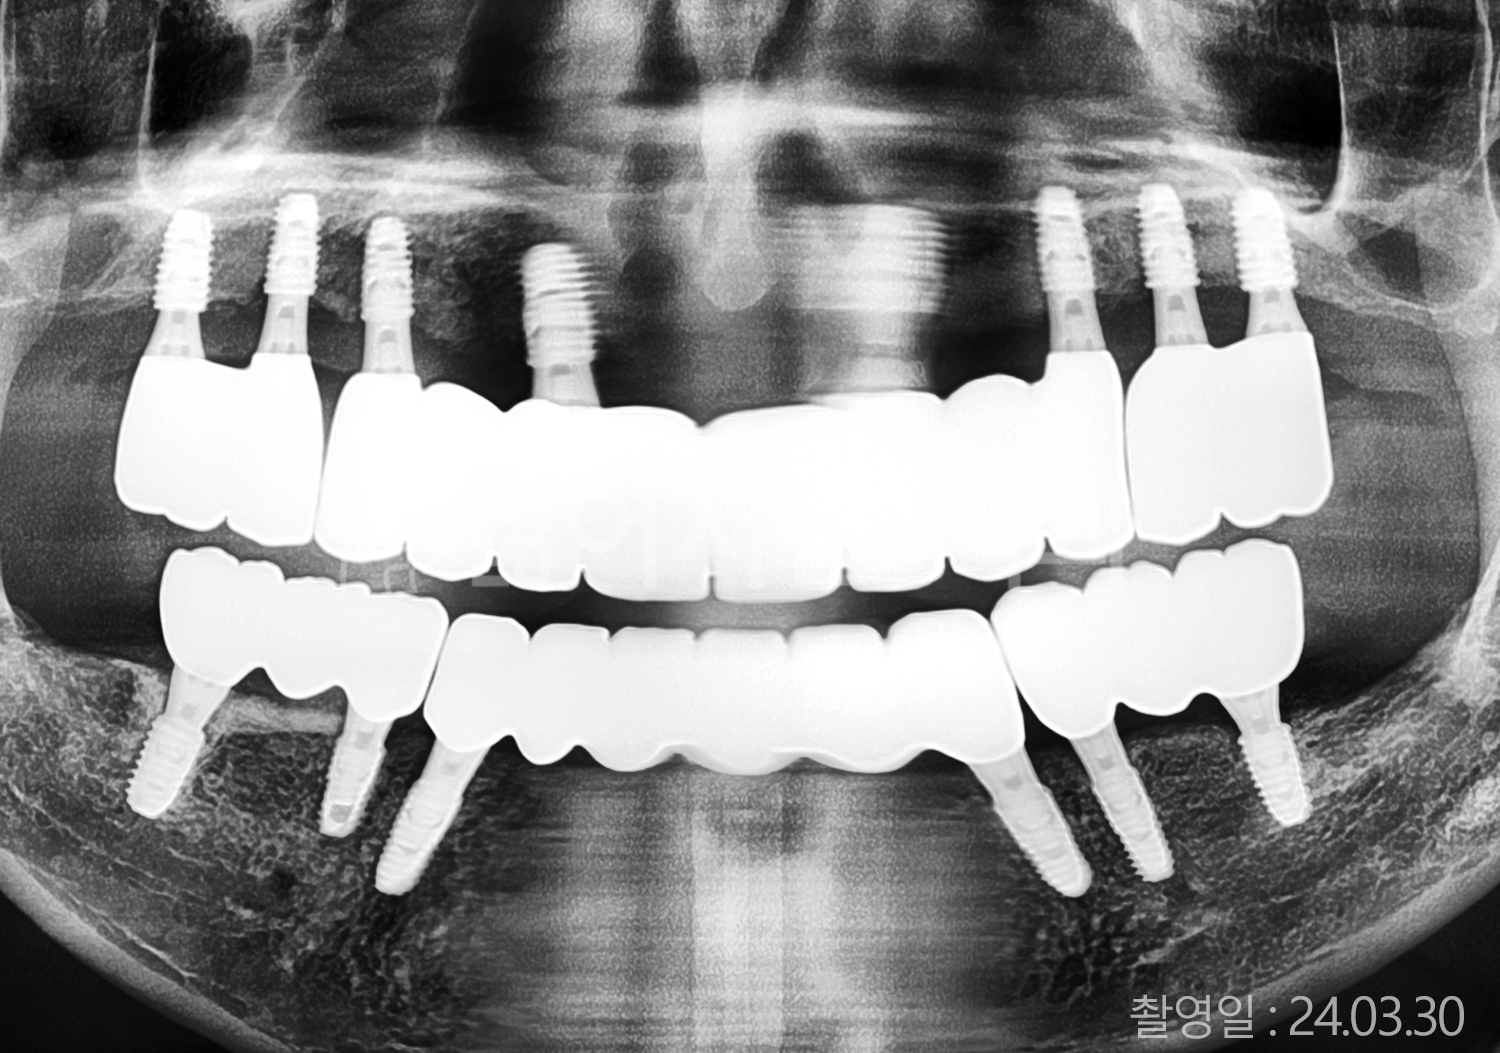

• 40대 전체치아 10개 이상 임플란트

• 50대 전체치아 10개 이상 임플란트